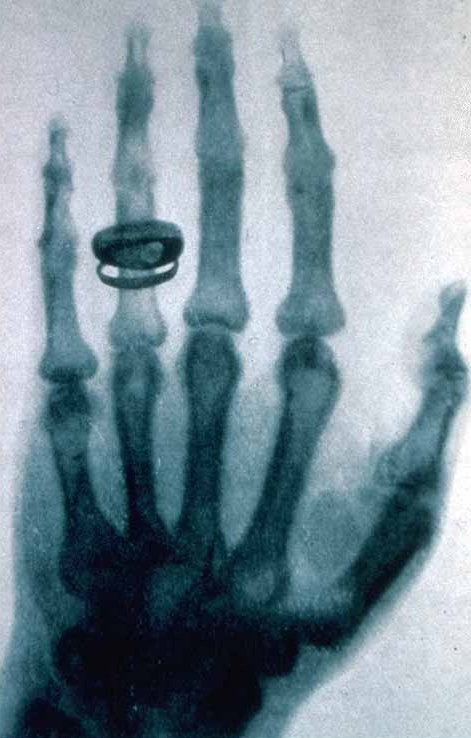

La notion de médecine préventive est fort ancienne mais il a fallu attendre le début du XXème siècle avec le développement de l’imagerie médicale pour pouvoir diagnostiquer les maladies, suivre leur évolution et ainsi pouvoir mieux les soigner puis prévenir et anticiper le développement de ces maladies. Les grandes innovations qui ont permis le développement de la médecine préventive sont tout d’abord la radiologie au Rayon X qui est apparue en 1885 et qui s’est affinée avec l’association de l’informatique qui a permis l’apparition du scanner. Dans un deuxième temps dans les années 1950 est apparu l’imagerie ultrasonore (basée sur l’effet Doppler) appelée l’échographie qui est une application au corps humain du sonar. Et enfin une troisième innovation essentielle est apparu dans les années 1970, il s’agit de l’imagerie par résonnance magnétique qui permet d’analyser en profondeur les parties molles du corps ,ses formes et ses anomalies. On dispose ainsi aujourd'hui de l’IRM (imagerie par résonnance magnétique),et de la TEP (tomographie par émission de positrons ) .

Ci-contre : première radiographie de Wilhelm Rontgen, "inventeur" des rayons X.